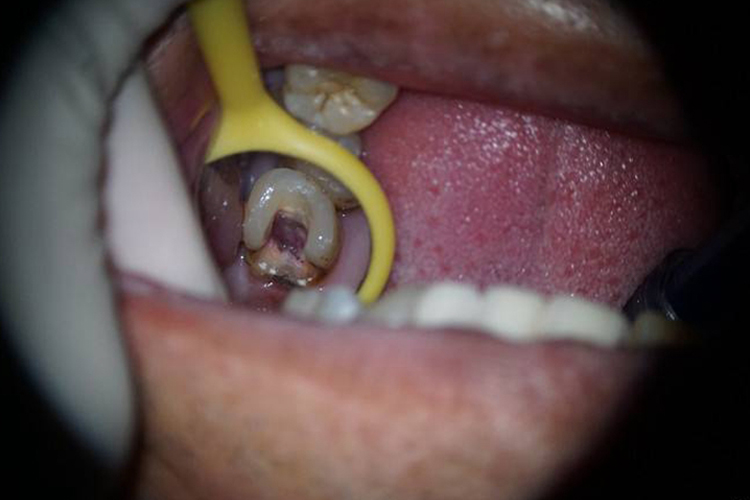

牙髓腔穿孔表现为牙髓腔和牙周组织相交通,对牙周组织产生机械性、化学性损伤,并发感染后容易导致根尖周病变的迁延不愈,严重的可导致牙体的破裂、折断。

牙髓腔穿孔患者应在医生指导下尽早阻断髓腔与牙周组织的交通,预防病变的扩大,促进病变组织的愈合。如果没有出现感染,应立即进行穿孔的修补封闭,同时预防创面的污染和出血。对于较大范围的穿孔,可根据患牙承受咬合力量的情况,部分也可采取牙根分离术或牙半切除术。